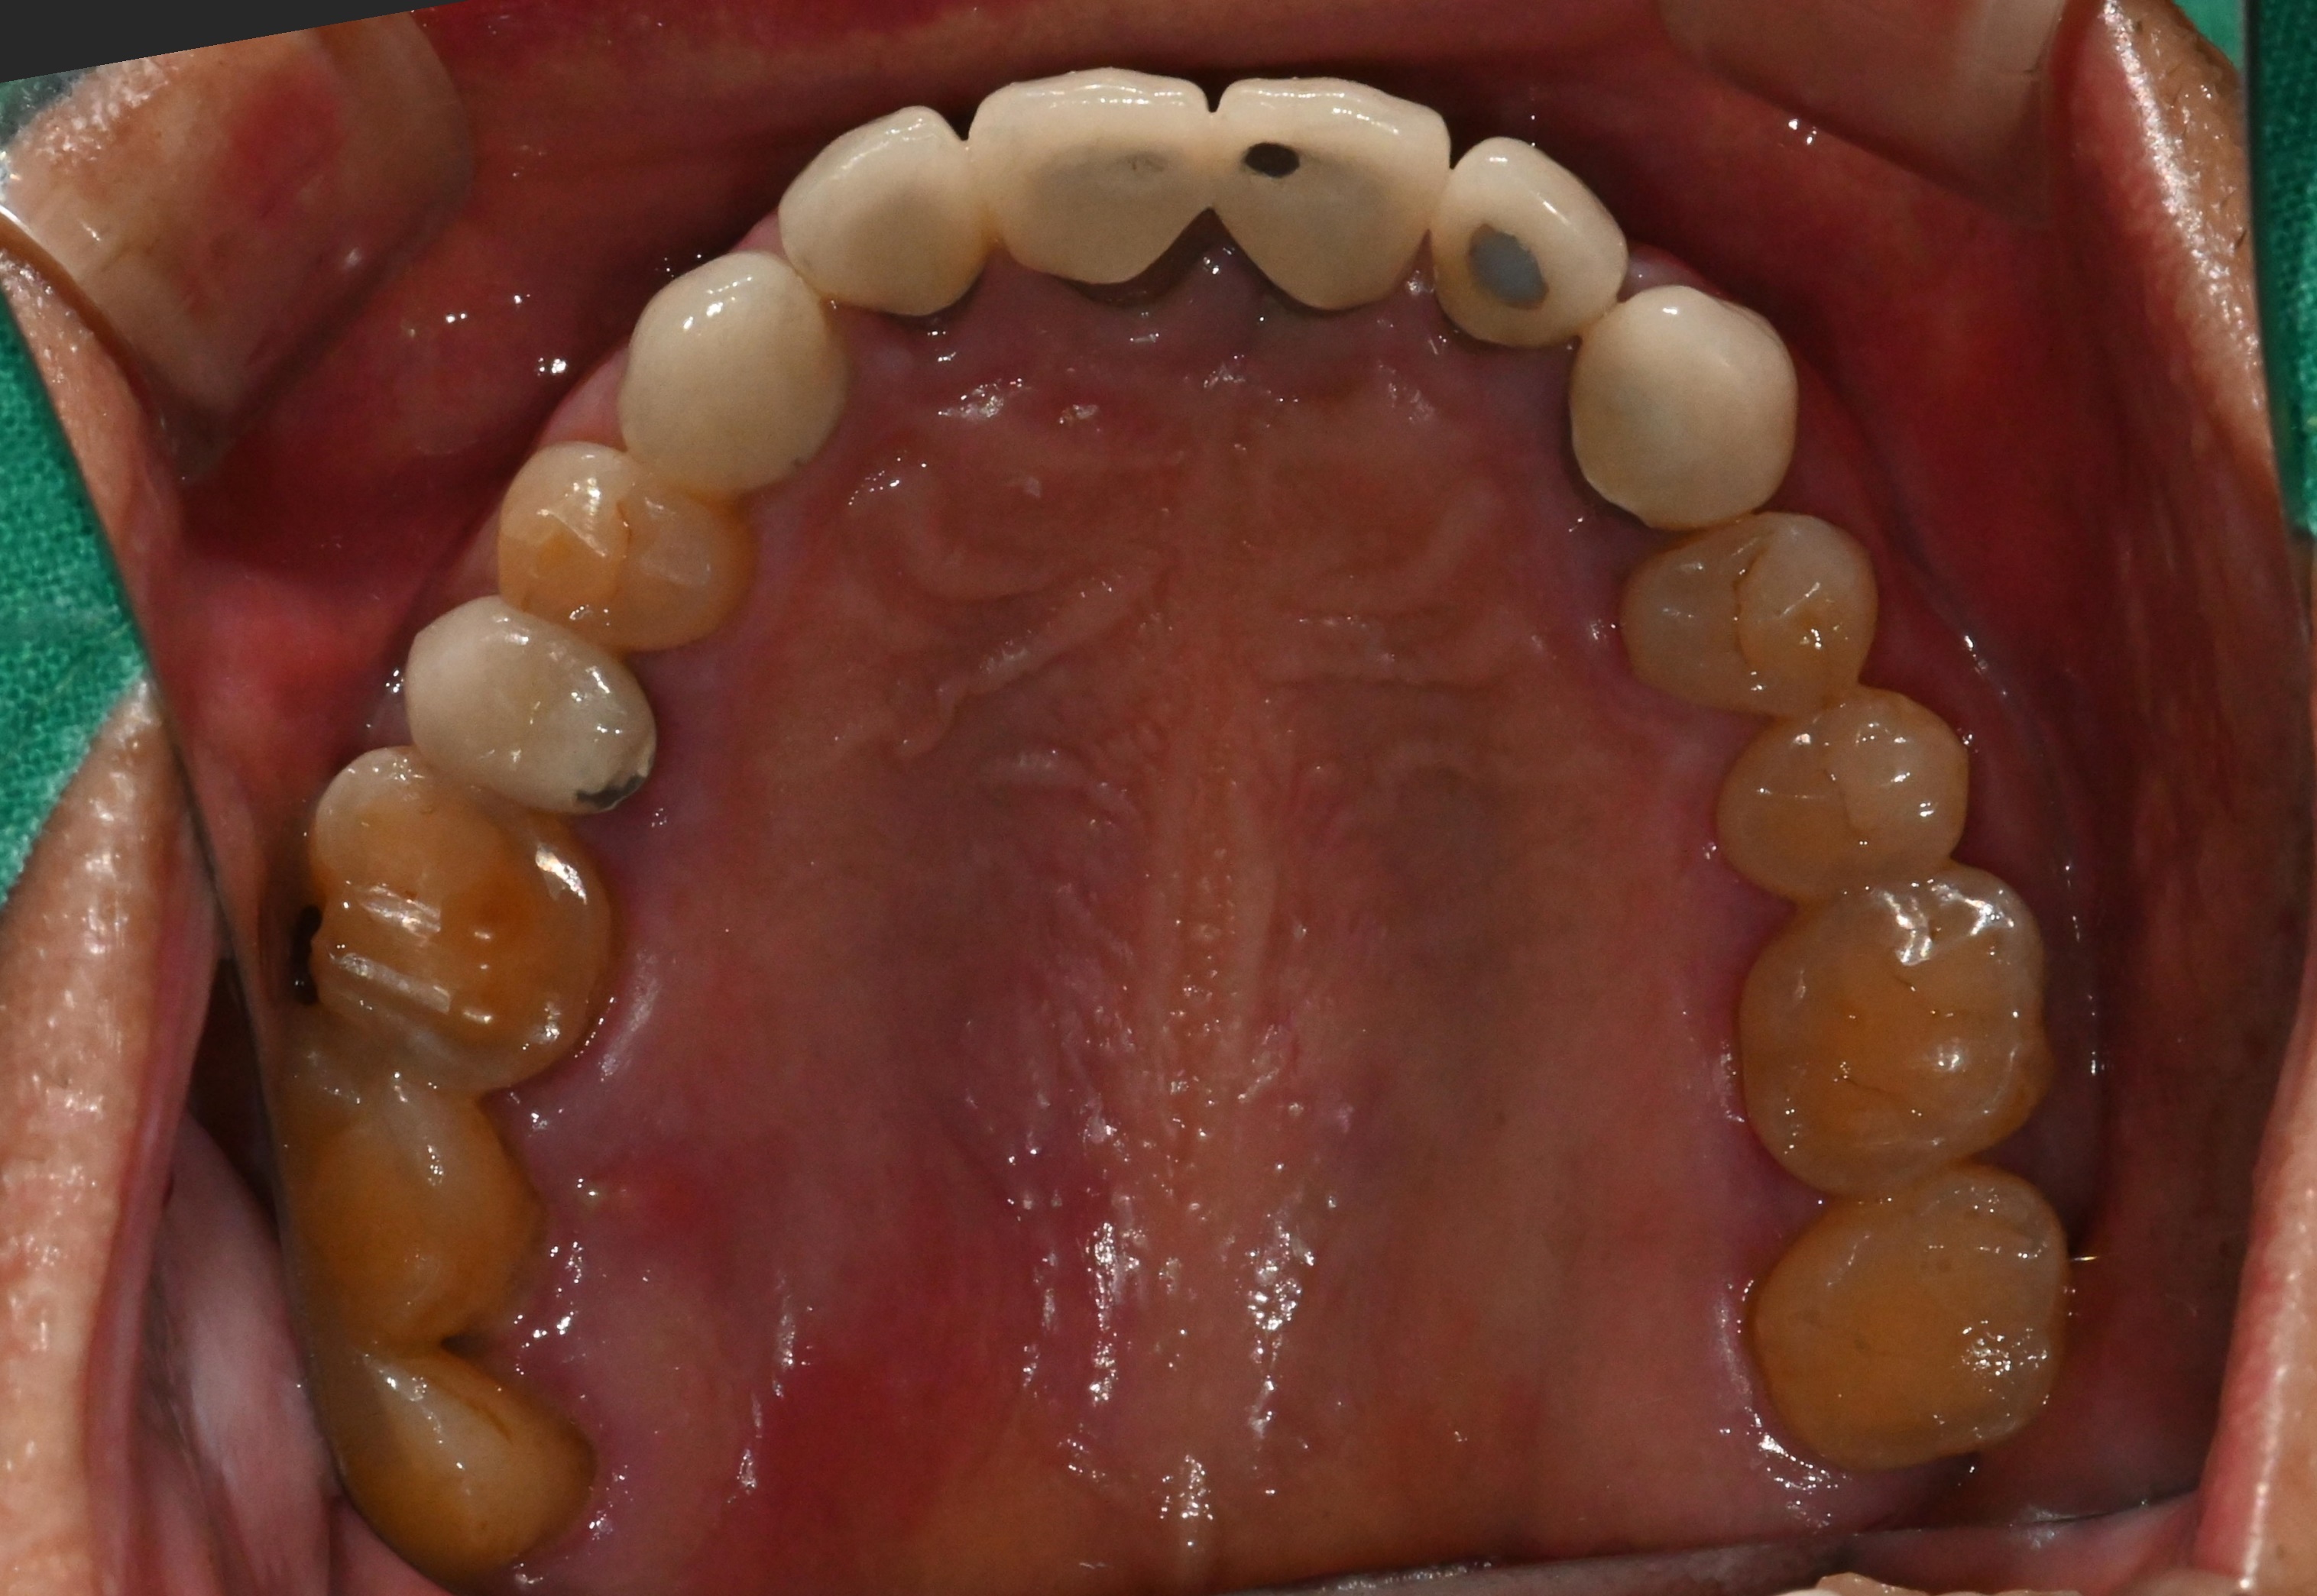

이 환자분은 5년 전에

일반적인 임플란트로

앞니 두개를 식립하셨습니다.

최근 보철물에서

냄새가 나고 흔들린다며 내원하셨죠.

진단해보니,

잇몸 색이 푸르딩딩하게 변해있네요..

이는 인공치변 주변 염증

진행되고 있다는 신호입니다.

방사선 사진에서는

픽스쳐 주변 뼈의 50% 이상이

이미 녹은 상태였습니다.